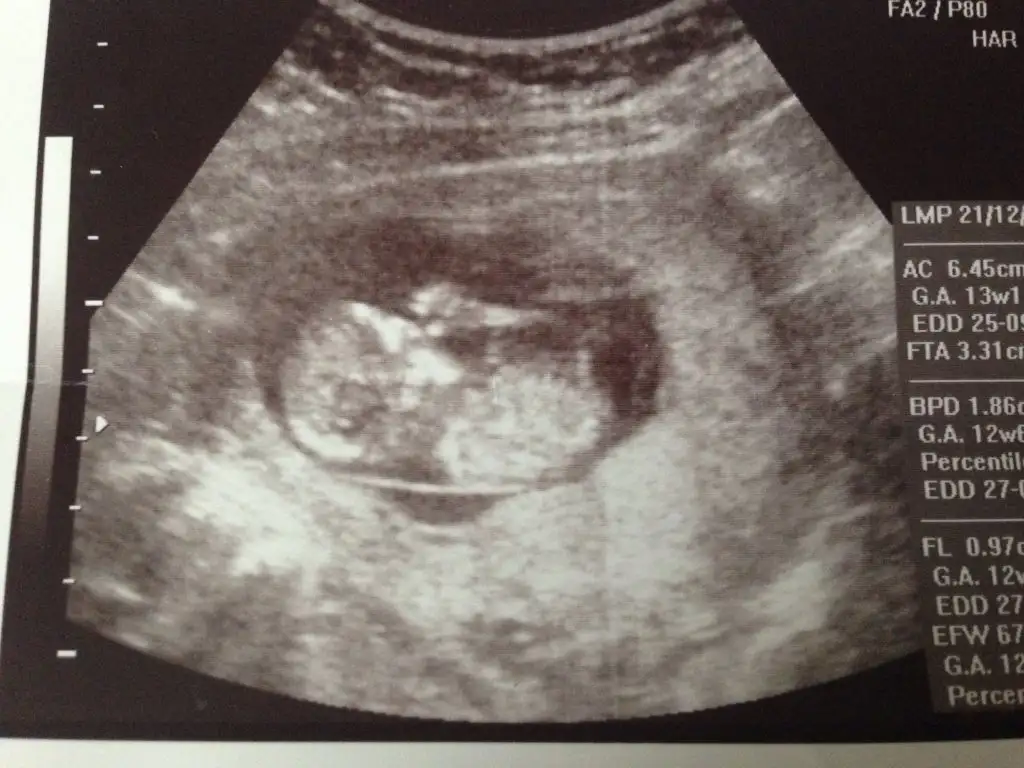

Kizlar bugun ultrasona girdim...radyoloji uzmani bakti..fotolari yukluyorum...o da erkek gibi dedi...once ki dr um kiz gibi...bacakarasi foto atiyorum bi bakabilir misiniz...dr a yarin gosterecem..Eki Görüntüle 1503752

Bu benim yavrunun 13. haftadaki hali. Ben pek bir şey anlamadım ama cinsiyet tahmini yapabilecek olan var mı?